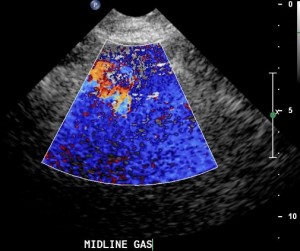

Bowel gas creates a typical artifact both in B-mode and in color flow mode. In B-mode bowel gas artifact looks like flashing lines that tend to obscure anatomical structures. In color flow mode bowel gas creates a disturbing array of random pixels that make it impossible to sample anything under them.

Bowel gas ultrasound artifact